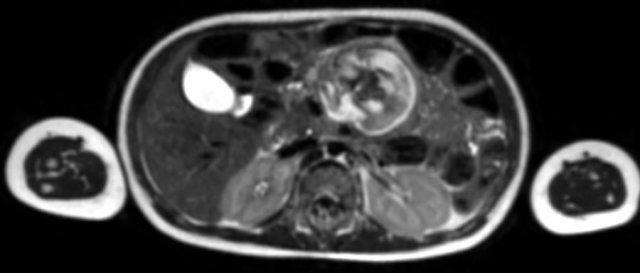

Mức độ lan rộng của khối u được đánh giá rõ ràng trên chuỗi xung TSE T2 weighted 3D theo mặt phẳng axial.

The left kidney is compressed and displaced caudally.

Có di căn hạch bạch huyết cạnh động mạch chủ (mũi tên vàng nhỏ).

Nguyên ủy của thân tạng và động mạch mạc treo tràng trên bị khối u bao quanh (đầu mũi tên).

Tĩnh mạch chủ dưới bị đẩy ra phía trước (mũi tên xanh).

Xẹp phổi hai bên ở vùng lưng thường được thấy trên MRI, vì việc kiểm tra được thực hiện dưới gây mê.